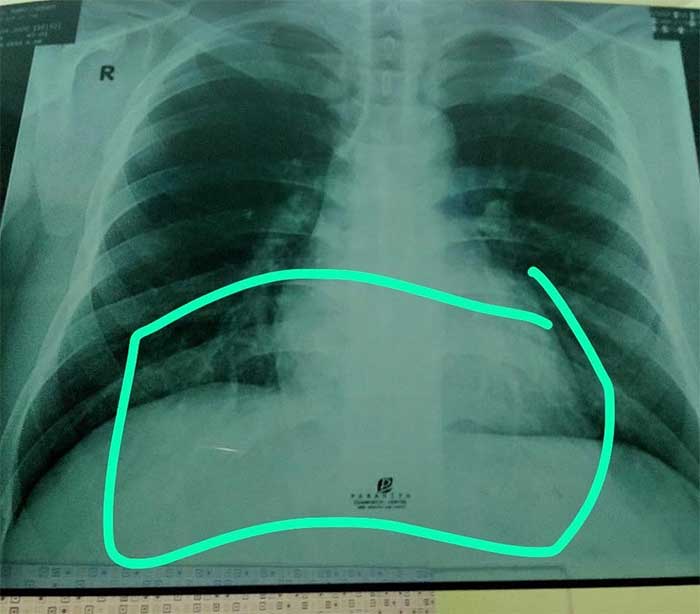

Di luar dugaan, ada bercak putih pada salah satu paru-paru sang adik yang menandakan ia menderita pneumonia. Diakui Via, jauh sebelum marak kasus corona, sang adik memang pernah mengalami sesak napas. Namun karena salah satu gejala penyakit corona adalah pneumonia, maka ia meminta sang adik untuk menjalani rapid test.

“Nah hasil paru salah satu adekku ada #pneumonia ,orang tua kuatir krn takut corona ( fyi aktifitas adekku hampir setiap hari ke surabaya anter jemput pacarnya kerja di Mall ) Akhirnya aku tanya ke beberapa spesialis paru dan semuanya bilang gpp ( itu gara2 rokok bla bla bla ) Adekku ini memang pernah sesek nafas jauhh sebelum adanya #corona Tp krn salah satu gejala corona adalah pneumonia, dirumah jg ada orang tua yg sakit Jadi untuk memastikan semuanya beneran baik2 ajaa, aku bawa dia rapid ke rs rujukan #covid19 dan hasilnya NON REAKTIVE,” tulis Via mengiringi hasil rontgen paru-paru adiknya yang ia unggah di Instagram, Minggu (24/5) kemarin.